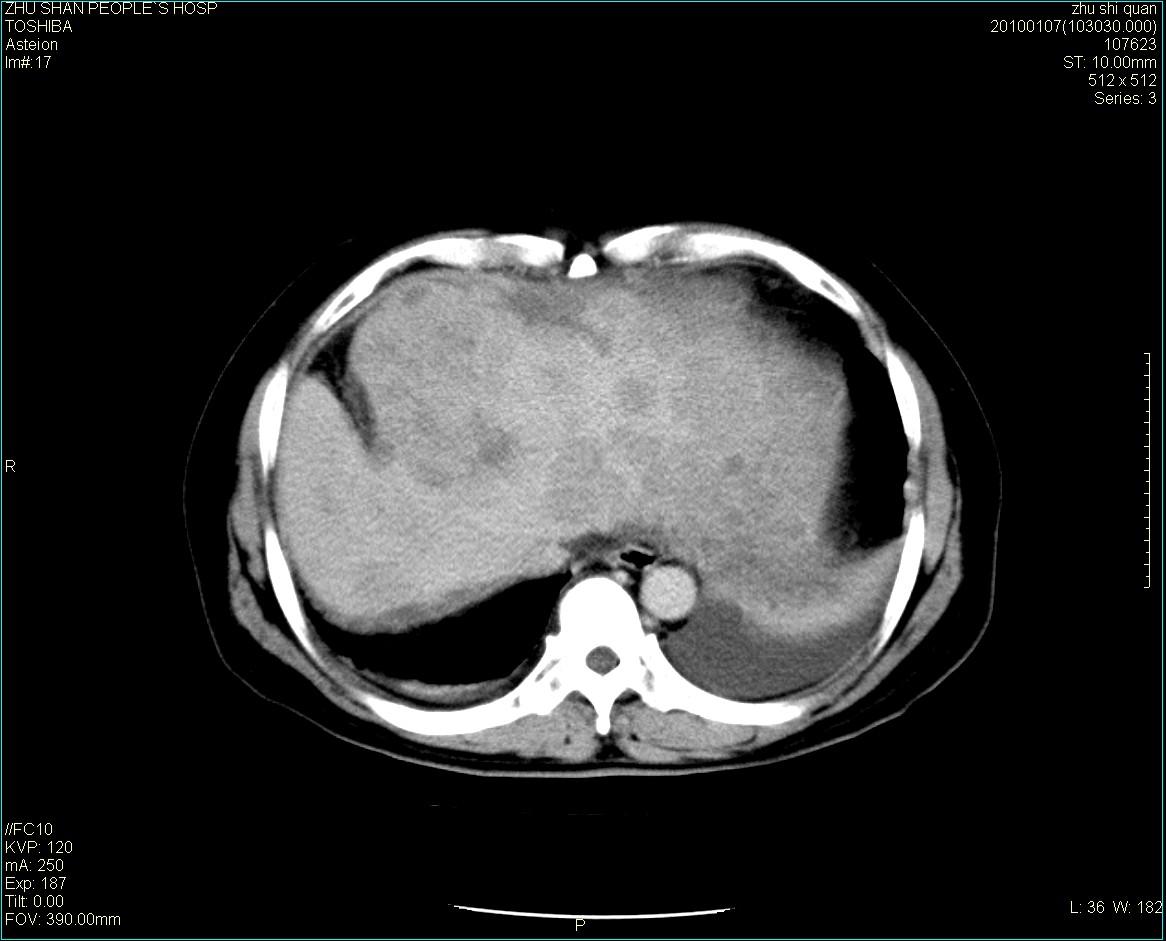

男性病人 肝ca两次术后,今日复查。

1)肝癌并多发性转移。2)双侧胸腔积液(以左侧为甚)伴左下部分肺萎陷。

肝癌术后复发,肝内、脾脏、腹膜后及腹膜多发转移,腹水,双侧胸腔积液(以左侧为甚)伴左下膨胀不全。

肝癌术后复发,肝内、脾脏、腹膜后及腹膜多发淋巴结转移,腹水,双侧胸腔积液。